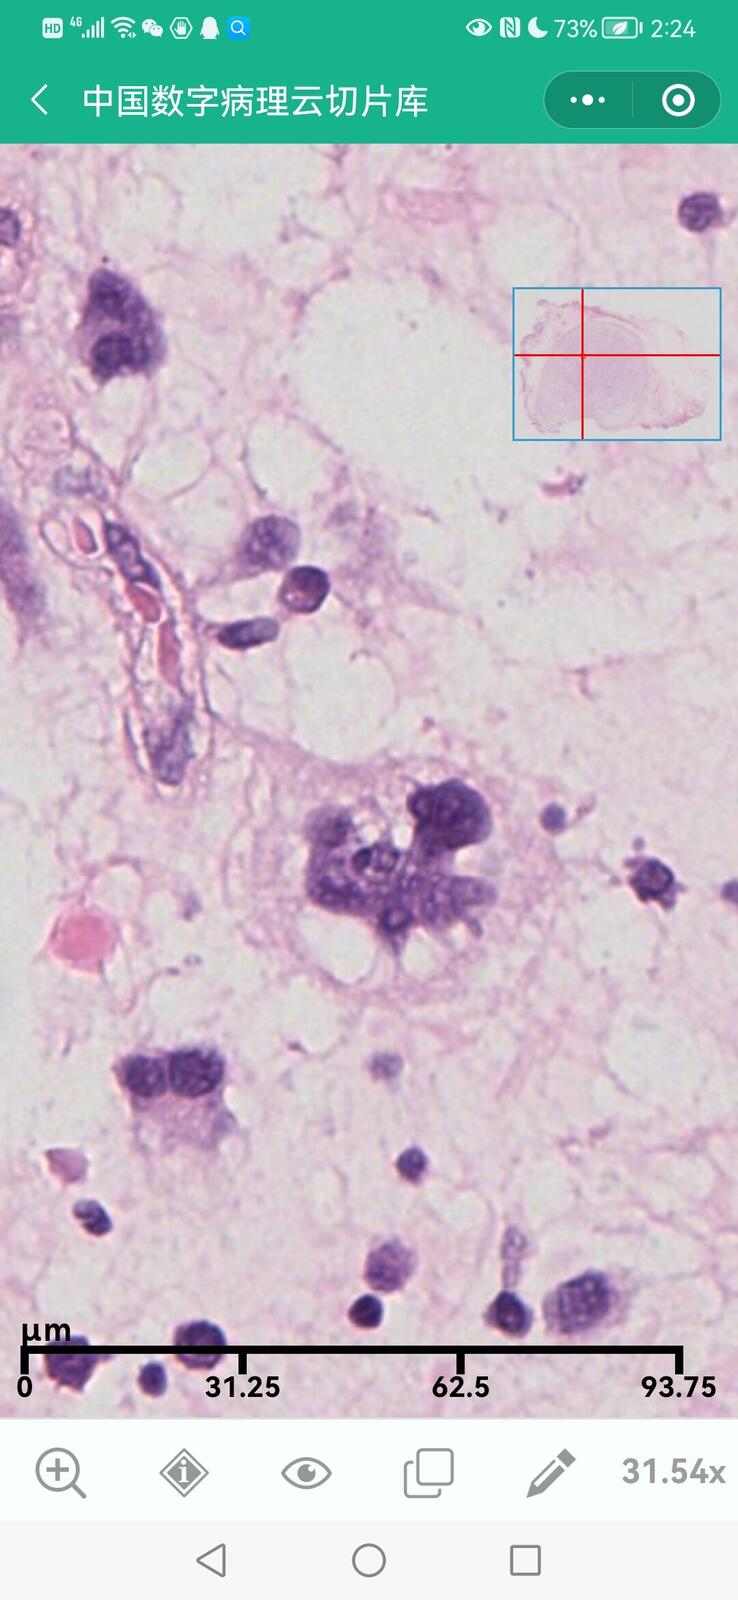

乳腺黏液性囊腺瘤伴导管内癌